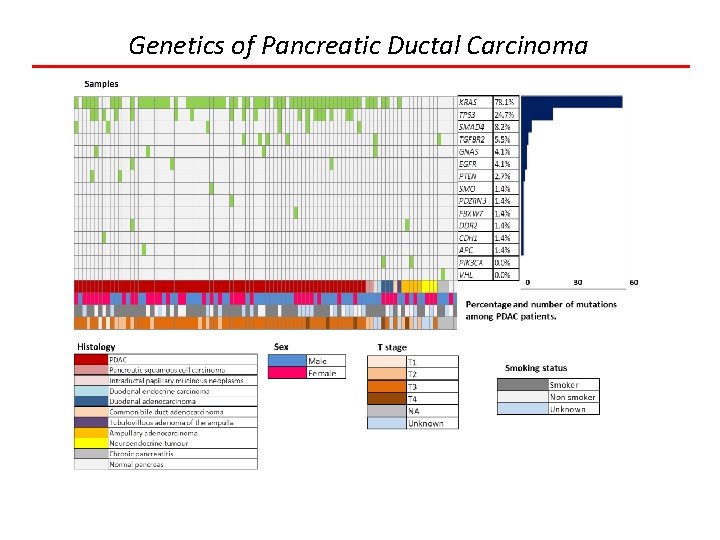

Genetics of Pancreatic Ductal Carcinoma